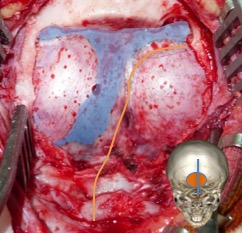

craniotomie et contrôle de la veine émissaire du torcular

les avantages de la craniotomie par rapport à la craniectomie sont la rapidité, le bon contrôle des sinus et de la veine émissaire du torcular (ci-contre), et une fermeture d’excellente qualité. sur le plan esthétique, le résultat est également bien meilleur, ce qui compte chez ces patients alopéciques après irradiation (Cf. ci-dessus).